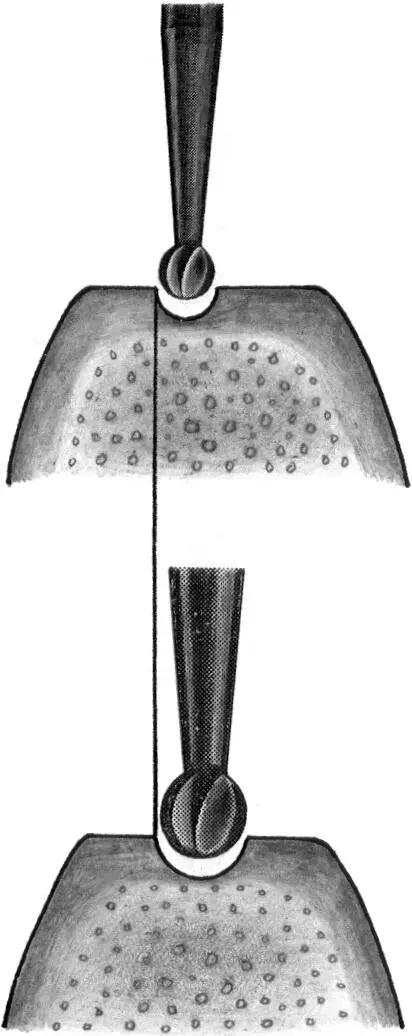

Fig 1-5Varying sink depths.

Fig 1-5a The 3.5-mm-diameter depth gauge is inserted so that the middle of the 12-mm mark is aligned with the bone crest (left) . When the standard implant is inserted, this allows the rough border to be aligned exactly at the crest (right) .